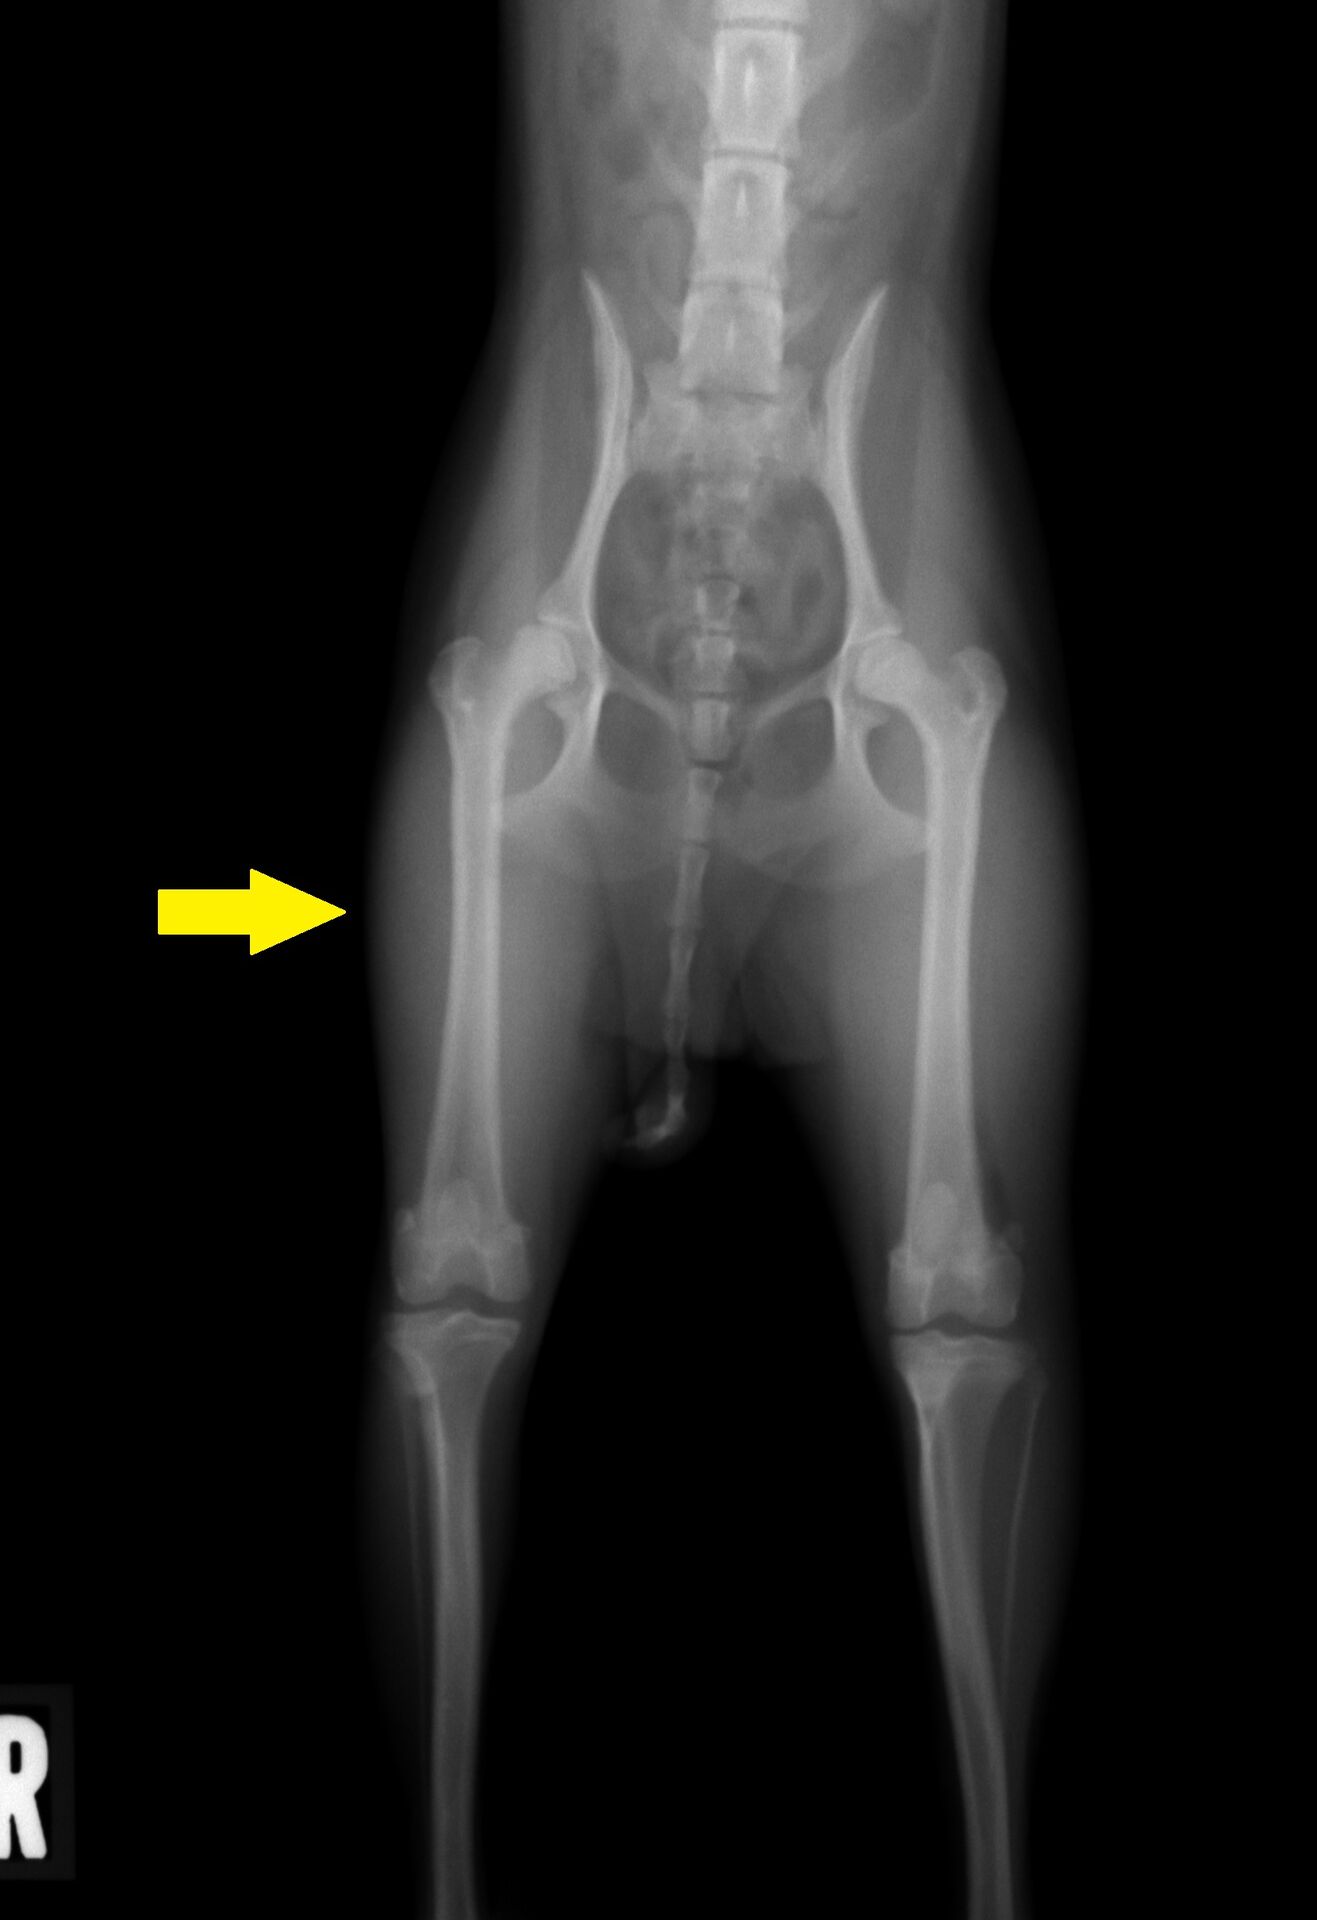

その結果が下の写真です。

わかりにくいのですが、左の写真 中央部に股関節(骨盤と大腿骨が接している

部分の関節)に隙間 (黄色矢印) があります。普通はもっと狭いのですが、症例はかなり広く

なっています。この画像からレッグペルテスと判断しました。この関節は放っておくと

どんどんひどくなり、患肢を使わなくなっていきます。現に右の写真で、右脚の大腿部の

筋肉が細くなっています(黄色矢印)ので、あまりこの脚をあまり使っていないため

筋肉が萎縮し始めています。治療が遅れると、治療後も脚を使わなくなってしまうことが

あります。